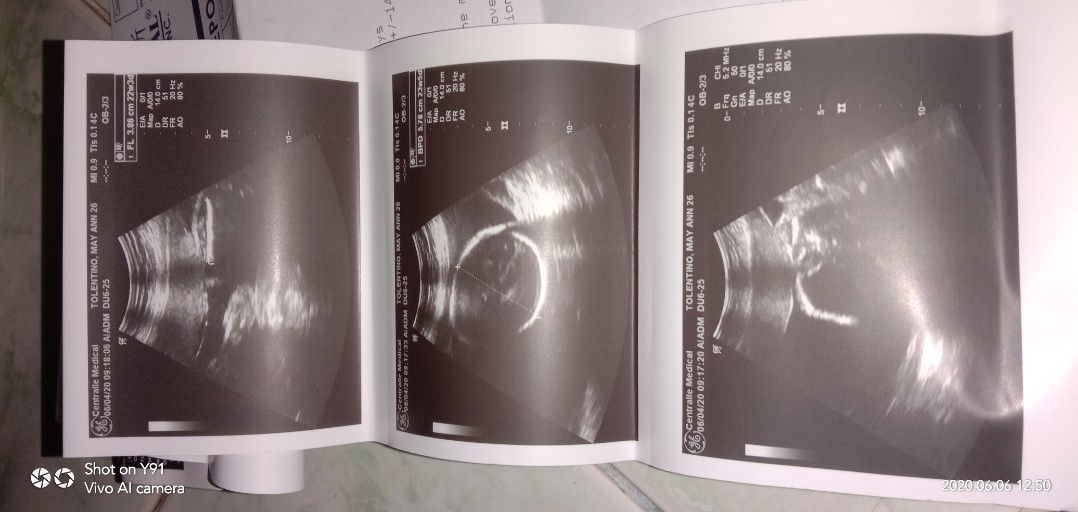

Hello mga.momshie.. Ako po yung nagtanong last time if pwede magkamali ang ultrasound sa gender lalo n at breech yung baby.. Ito po yung ultrasound ko... Boy daw po... Akala po tlaga nmin eh girl na... Pwede po kaya tlaga magkamali pag ganyn yung pwesto ni baby???